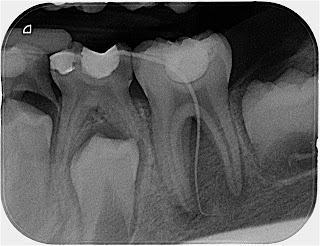

Caso clínico Master: ¿Quién dijo fisura?

Caso clínico Master: La “Grande Bellezza” de la anatomía interna de un molar permanente joven

Caso clínico Master: 3 conductos de PM